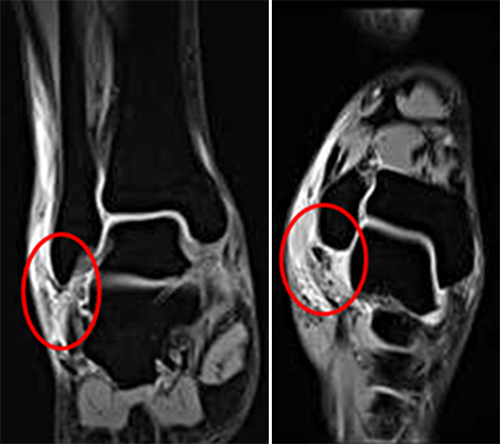

1단계: 경미한 부종, 압통이 있으나 불안정성이나 기능적 상실은 거의 없는 인대 내부의 파열

2단계: 중등도 부종, 압통 및 움직임 제한을 동반한 인대의 부분 파열

3단계: 관절의 불안정성과 함께 심한 부종, 압통 및 관절운동제한이 있는 완전한 파열

1단계 염좌는 스프린트 고정 및 보존적인 치료로 호전을 기대할 수 있으나 2단계 이상에서 관절의 불안정성이 있으면 관절경적 봉합술이 필요